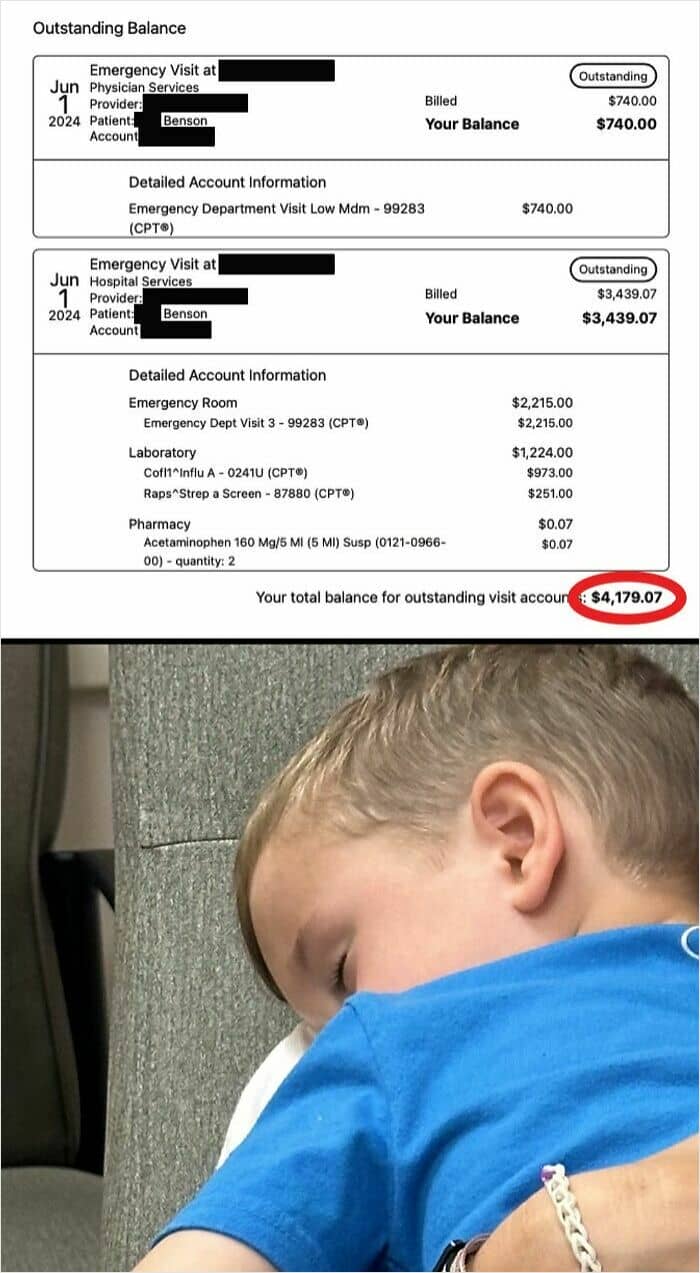

#59 Had To Take My 3 YO Son To The ER Last Week. Fear Was Appendicitis But After 45 Min Of Moaning He Burped For 5 Seconds & Was Fine So We Asked To Leave. The Bill? $4,179

I called the hospital billing dept. You won’t believe how this ends. Here’s the breakdown: $2,215 – “The visit” $740 – 2 min visit with the doc $1,224 – “Standard” nurse’s swab of my son’s throat & nostrils for covid/strep test $0.07 – Tylenol (how generous) I proceed to tell them (politely) that the same “tests” are $50 at a pharmacy down the road & they weren’t even related to my son’s symptoms. There must be a mistake. Nope. I tell her we’re technically “cash pay” (we are members of a healthcare sharing org), and ask if there is a cash-pay discount. She says, “Yes. Let me calculate it for you.” Cash pay price: $685 TOTAL Of course, I’m relieved personally, but I can’t help but think… THIS is why millions are paying insane amounts in insurance premiums every month. ERs/hospitals are out of control. Can someone make this make sense?